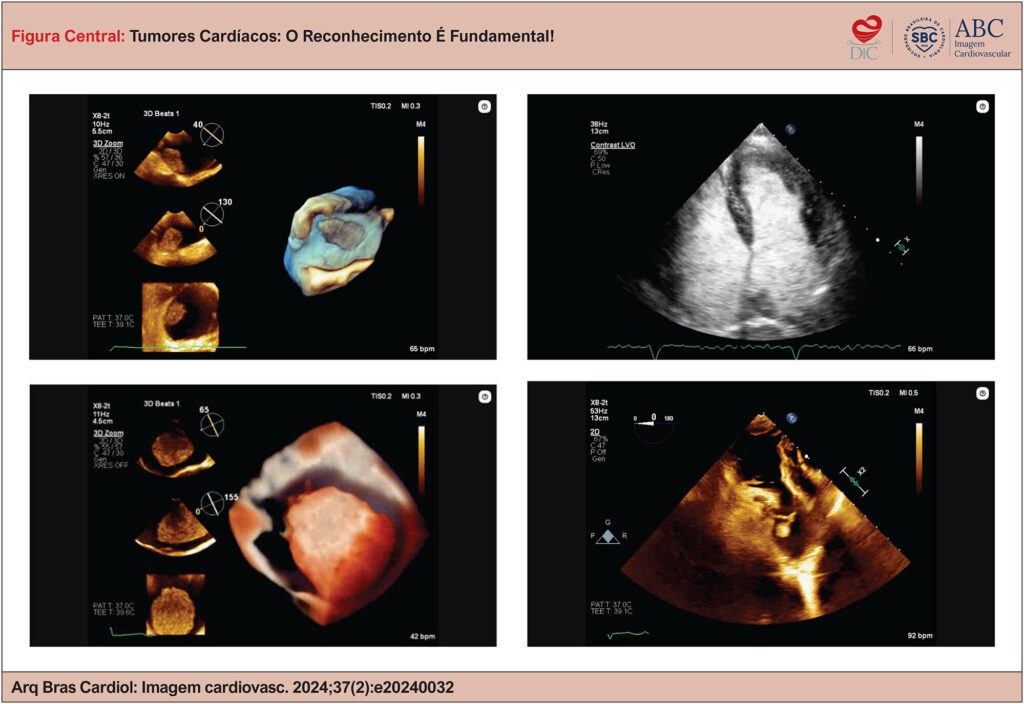

Tumores Cardíacos: O Reconhecimento É Fundamental!

Embora tumores cardíacos sejam raros e frequentemente encontrados de forma acidental, podem estar associados a sintomas constitucionais, cardíacos ou embólicos. Portanto, esses sintomas devem ser sempre considerados nas hipóteses diagnósticas para auxiliar na sua diferenciação. O ecodopplercardiograma tridimensional (3D) e o agente de realce ultrassonográfico apresentam-se como recursos diagnósticos adicionais e podem ajudar a determinar a melhor abordagem cirúrgica, caso seja indicada.